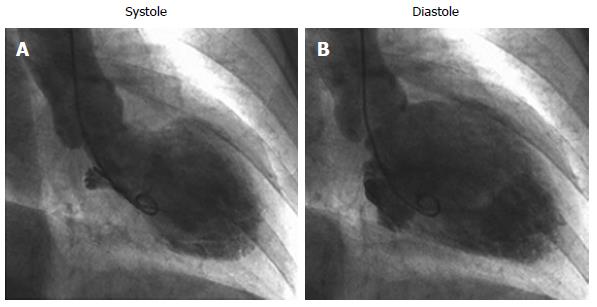

The name for this cardiomyopathy is taken from the Japanese name for an octopus trap, which has a shape that is similar to the apical ballooning seen on the following LV gram:

What is Takotsubo Cardiomyopathy?